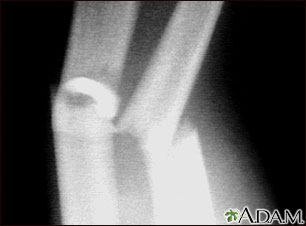

This x-ray shows broken (fractured) forearm bones (radius and ulna).